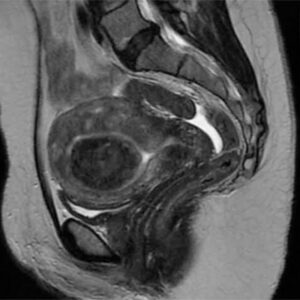

Uterine Fibroid Embolization